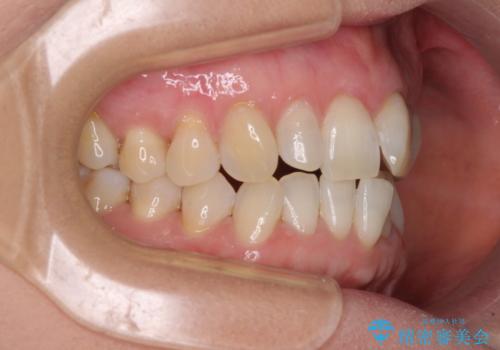

前歯のスペースが気になる インビザラインによる矯正治療

- 前歯の上下スペースによる食べにくさを気にして来院された患者様です。

インビザラインにより上下の前歯の隙間を閉じていくこととしました。

舌の突出癖があると上下前歯にスペースが開くため、矯正治療を機会に舌癖を改善するトレーニングを行ってもらい、矯正治療後の後戻りを防止するように指導しています。